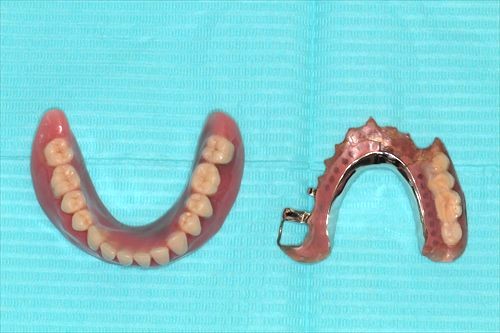

義歯が入ったところです。

義歯を外したところです。歯に内冠と呼ばれるかぶせ物を装着し、その上に義歯をかぶせていきます。

部分入れ歯の最終進化形態であり、これをもって部分入れ歯の歴史はほぼ終わり、インプラントへ移行したため、部分入れ歯としては最も咬めるものである事

たとえ残っている歯が無くなってもそのまま総入れ歯として使える事